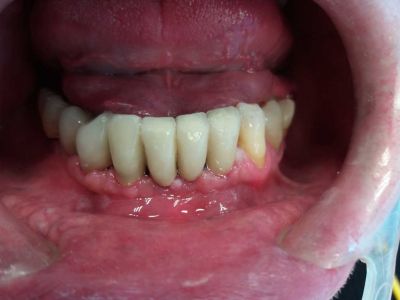

DOPO

Dall'inizio del trattamento alla consegna del lavoro definitivo il paziente ha sempre utilizzato un provvisorio fisso.

Durante la guarigione è stata eseguita anche una seduta di sbiancamento professionale.

A gengiva completamente guarita , dopo 3 mesi circa dall'inserimento degli impianti, è stato consegnato il lavoro definitivo.

Il paziente è rimasto molto soddisfatto e per noi questa è la cosa più importante.